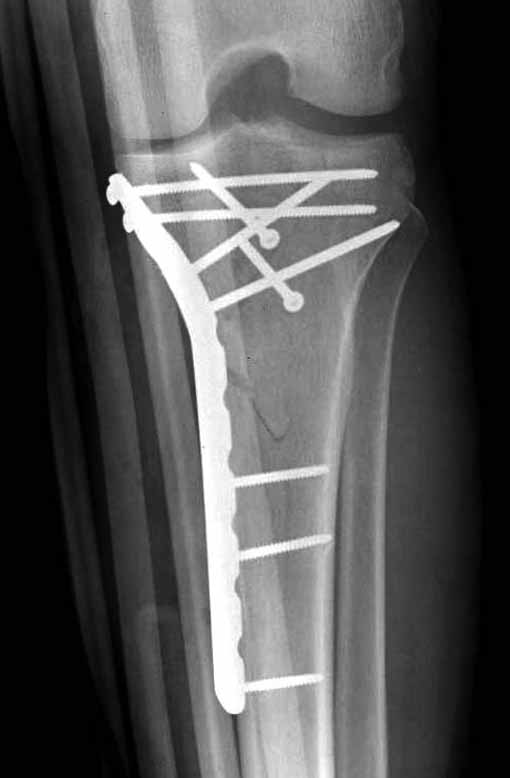

Для изолированных переломов медиального тибиал плато, фиксацию можно провести “медиальной пластиной”. Некоторые компании, например Smith & Nephew делают медиальные и медиально-задние пластины, но они мягкие, и легко можно создать нужный контур. Жесткость создается за счет фиксации жесткими пластинами, например экстра артикулярной пластиной для дистального плеча от Synthes. Медиальный доступ тоже не из легких, надо работать между pes and medial gastroc.

Частая ошибка, когда фиксацию двух колонного перелома проводят одиночной пластиной, т.е с одной стороны, и такая фиксация не удерживает, происходит вторичноое смещение. Необходимо нейтрализовать второй пластиной или дополнительным наружным фиксатором.

Если у вас, кроме пластины, нет другого альтернативного варианта, тогда, учитывая мягкотканые проблемы с наружной стороны, я бы рекомендовал операцию делать в два этапа. Преимущества, сперва репозиция и фиксация перелома с медиальной стороны, а затем, после улучшения состояния мягких тканей, зафиксировать с латеральной стороны. Современные пластины имеют латеральный Jig для перкутанных мини доступов.

В приложении этапы фиксации Both Column Fx и пластиной Synthes для плеча при переломе медиального мыщелка.